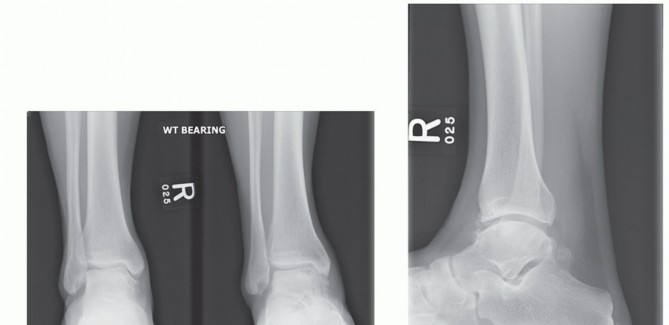

Preoperative weight-bearing radiographs suggest large medial OLT and varus malalignment with some varus talar tilt (TECH FIG 5A,B).

CT demonstrates large-volume medial OLT (TECH FIG 5C-E).

- TECH FIG 5 • A,B. Preoperative radiographs. A. AP and mortise ankle views suggest large medial talar dome OLT and varus alignment. B. Lateral radiograph. C-E. Preoperative CT of largevolume OLT. C. Coronal view. D. Sagittal view. E. Axial view.